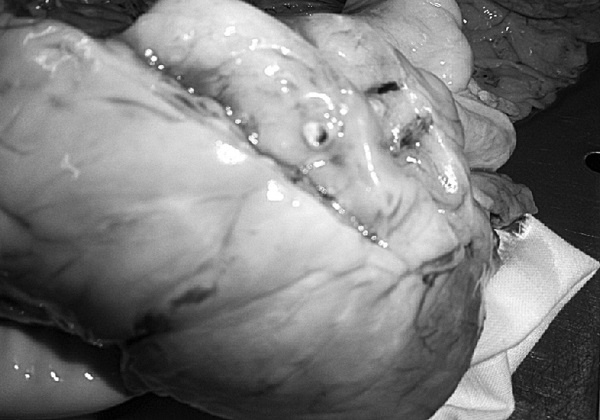

Доброкачественная гиперплазия предстательной железы

Рис. 1. Результаты аутопсии больного 68 лет